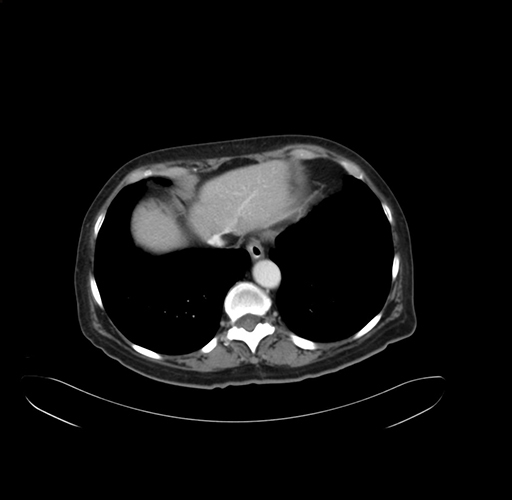

Pre-Chemo: Axial Venous